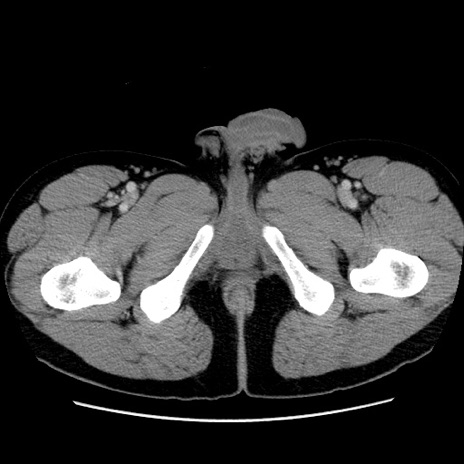

症例4(横断像)

【症例】30歳代男性

【主訴】腹痛、嘔吐

【現病歴】昨晩から突然の腹痛あり、その後嘔吐、軟便も出現。腹痛が改善しないため救急搬送となる。2日前にしめ鯖の食事歴あり。

【身体所見】意識清明、苦悶様、BP 135/90mmHg、BT 35.7℃、腹部:平坦、やや硬、心窩部〜臍部に自発痛、圧痛あり、筋性防御+、反跳痛-

【データ】WBC 8100、CRP 0.57